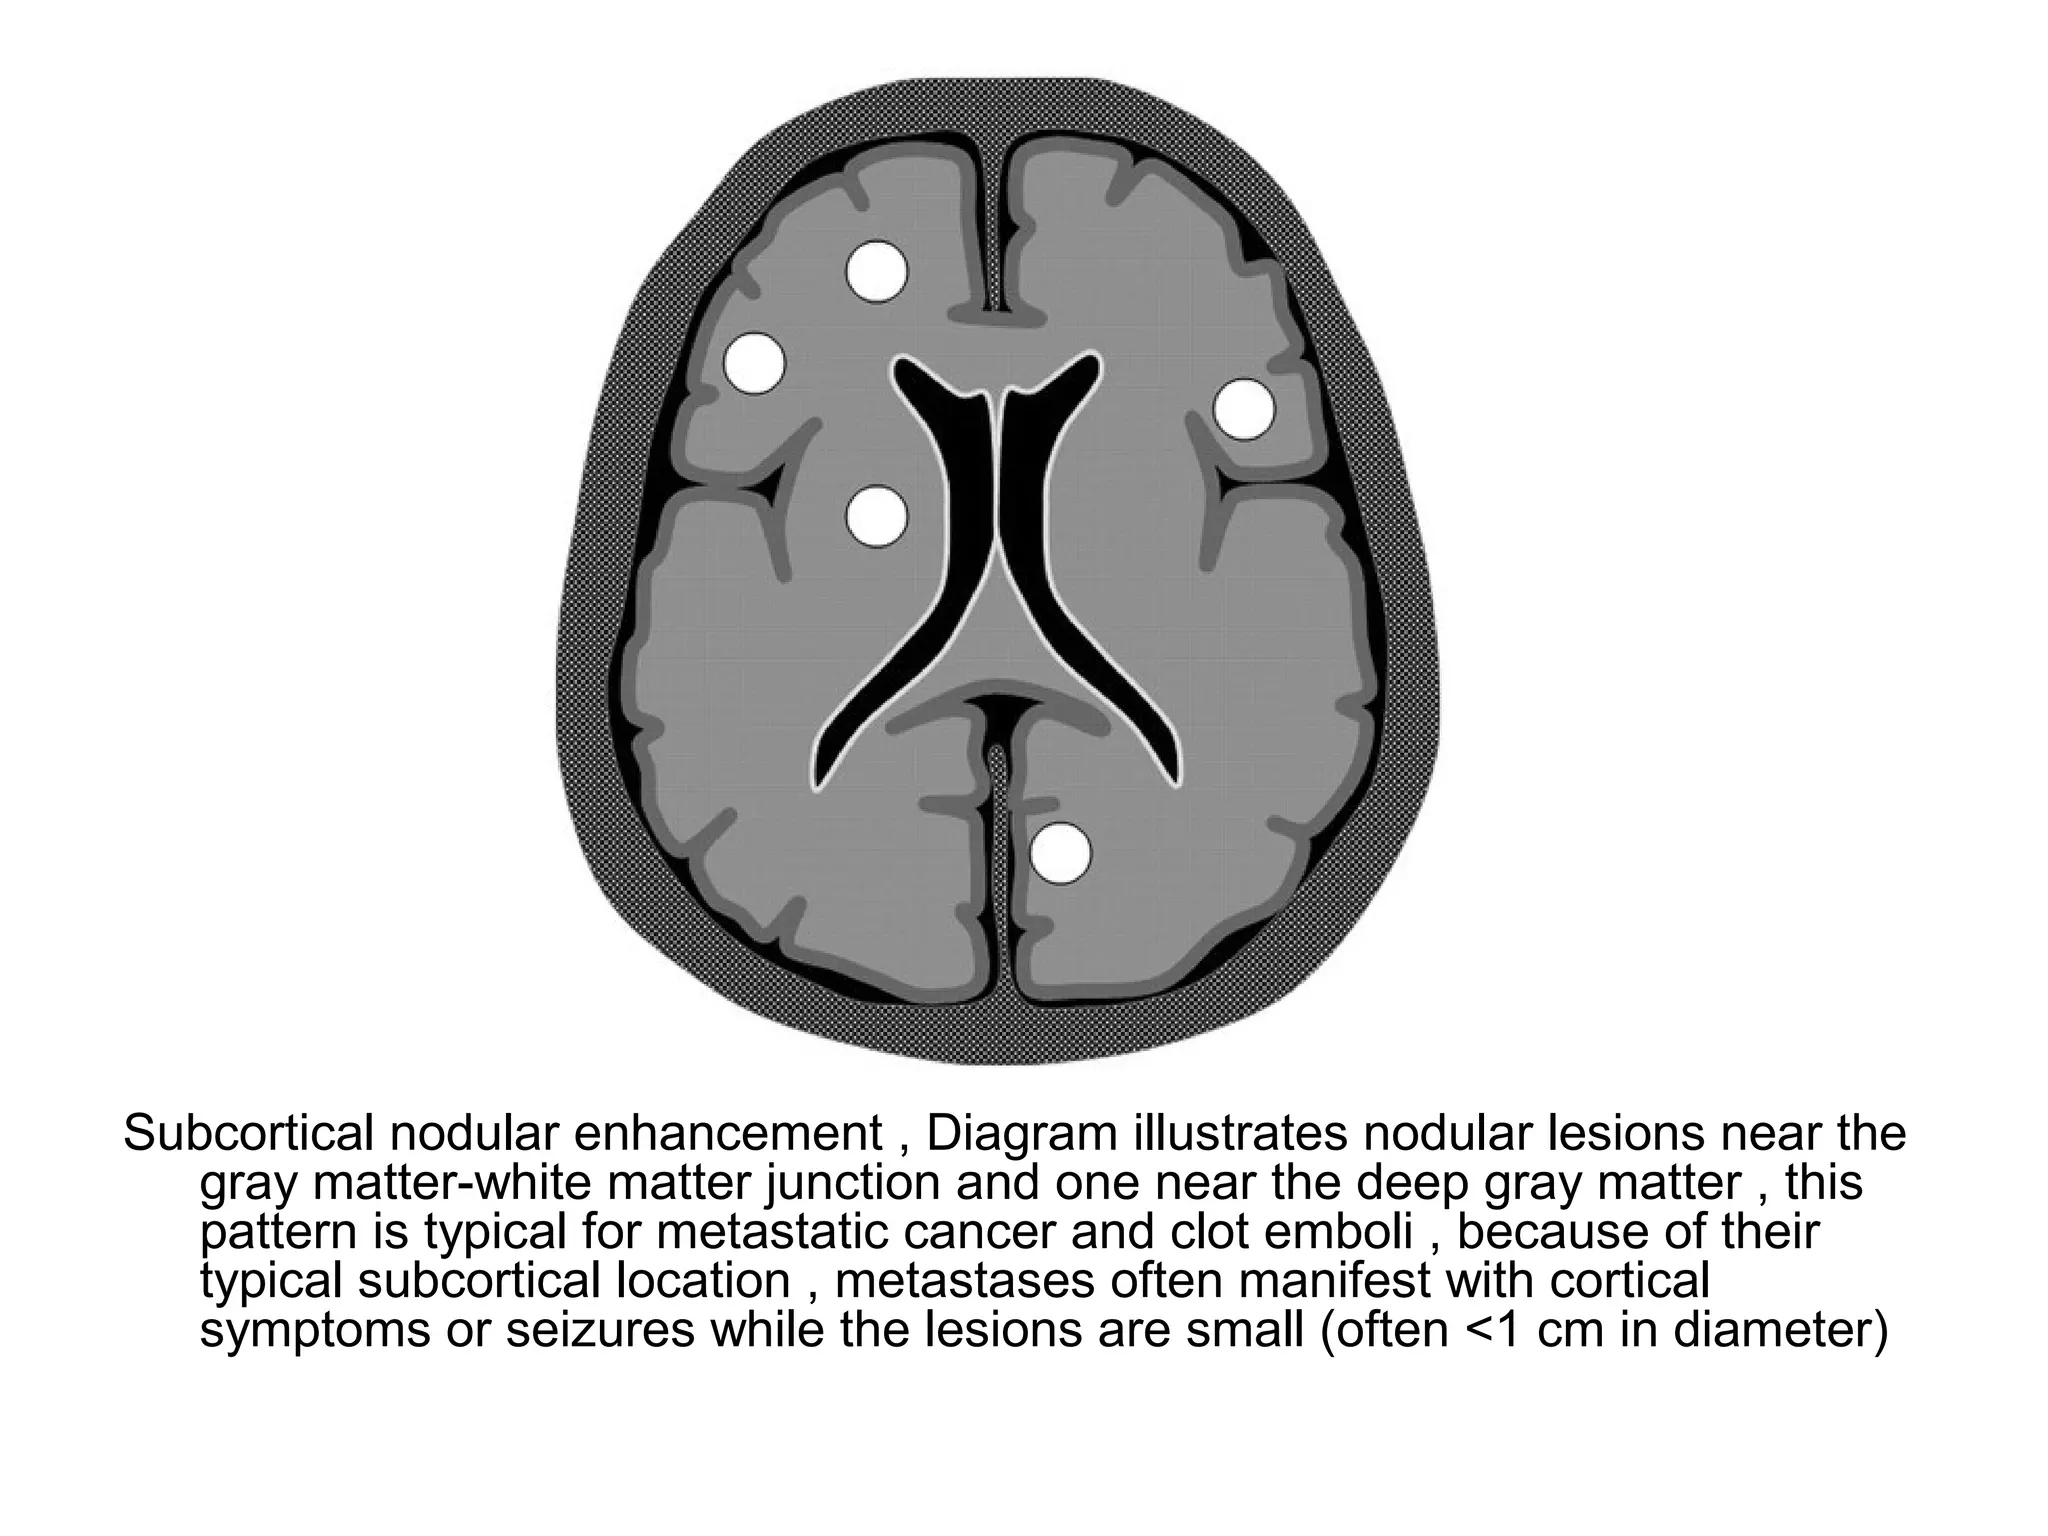

Subcortical nodular enhancement , Diagram illustrates nodular lesions near the

gray matter-white matter junction and one near the deep gray matter , this

pattern is typical for metastatic cancer and clot emboli , because of their

typical subcortical location , metastases often manifest with cortical

symptoms or seizures while the lesions are small (often <1 cm in diameter)